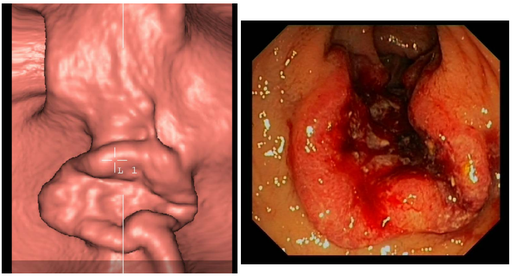

Cancers colo-rectaux

DANSE E. - UCL

Digestif MASTER 1